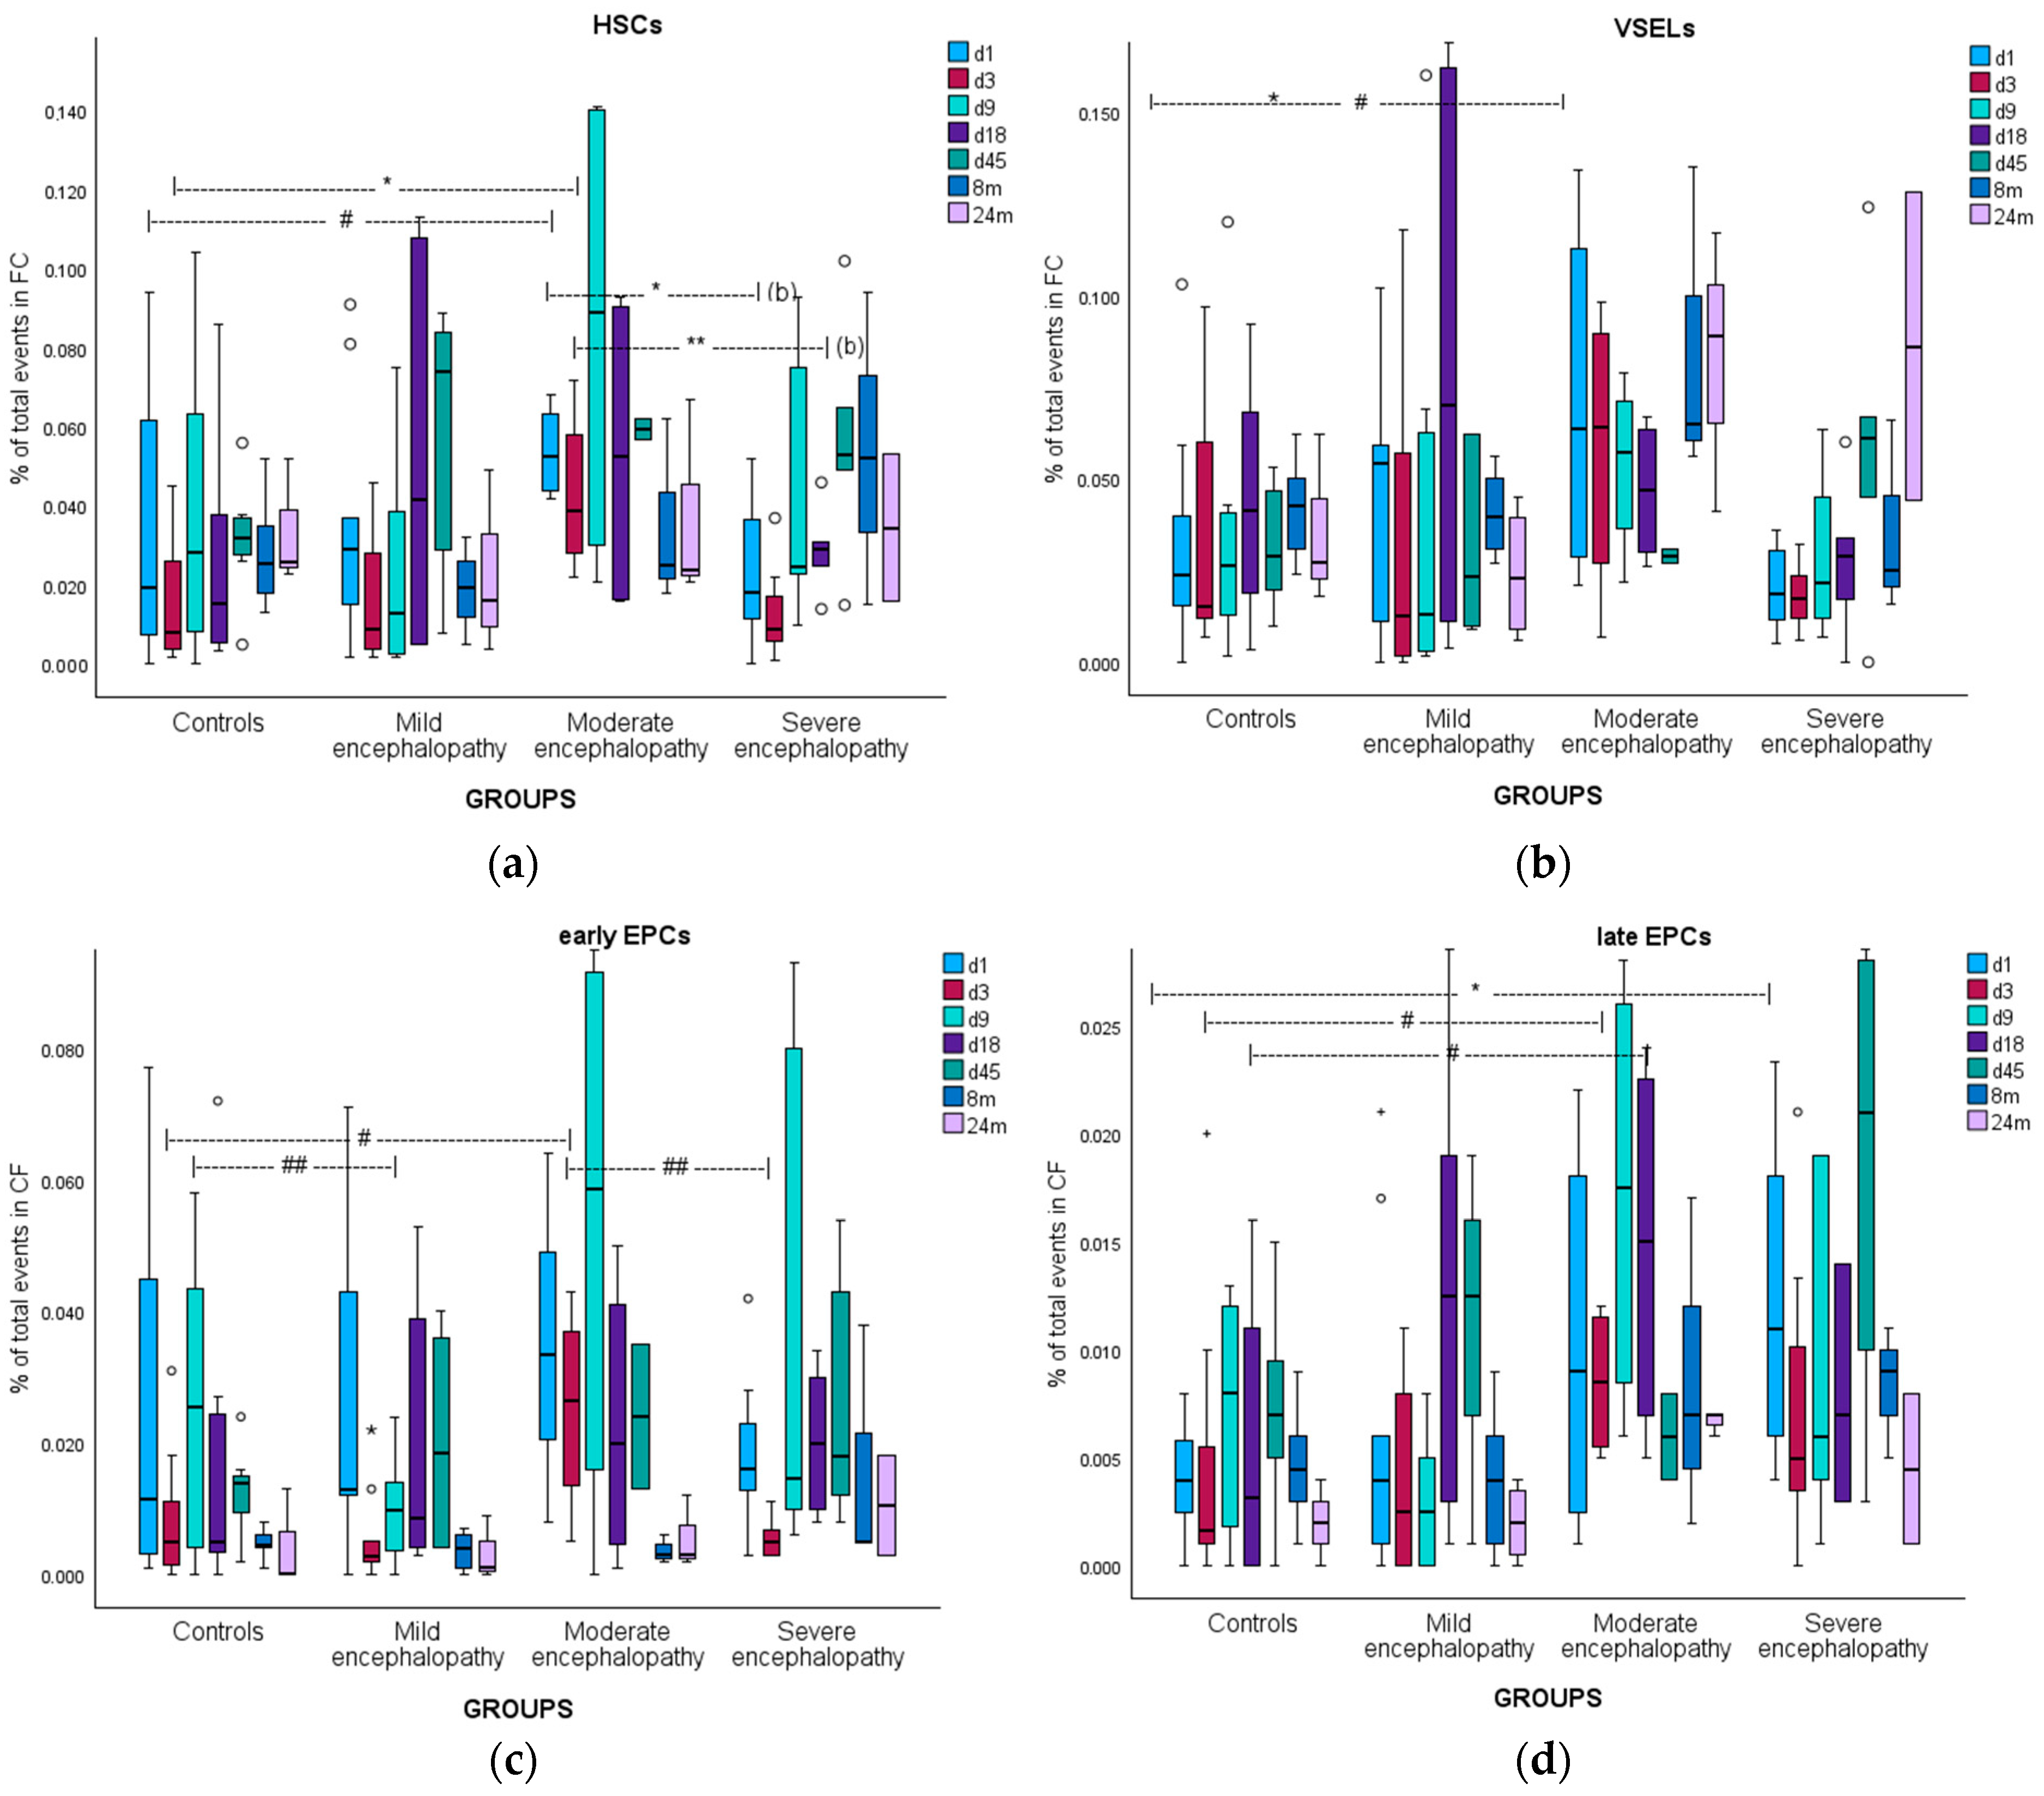

3.5. Hematopoietic Stem Cells

3.5.1. Kinetics

3.5.2. Correlations

3.6. Very Small Embryonic-like Stem Cells

3.6.1. Kinetics

3.6.2. Correlations

3.7. Early Endothelial Progenitor Cells

3.7.1. Kinetics

3.7.2. Correlations

3.8. Late Endothelial Progenitor Cells

3.8.1. Kinetics

3.8.2. Correlations